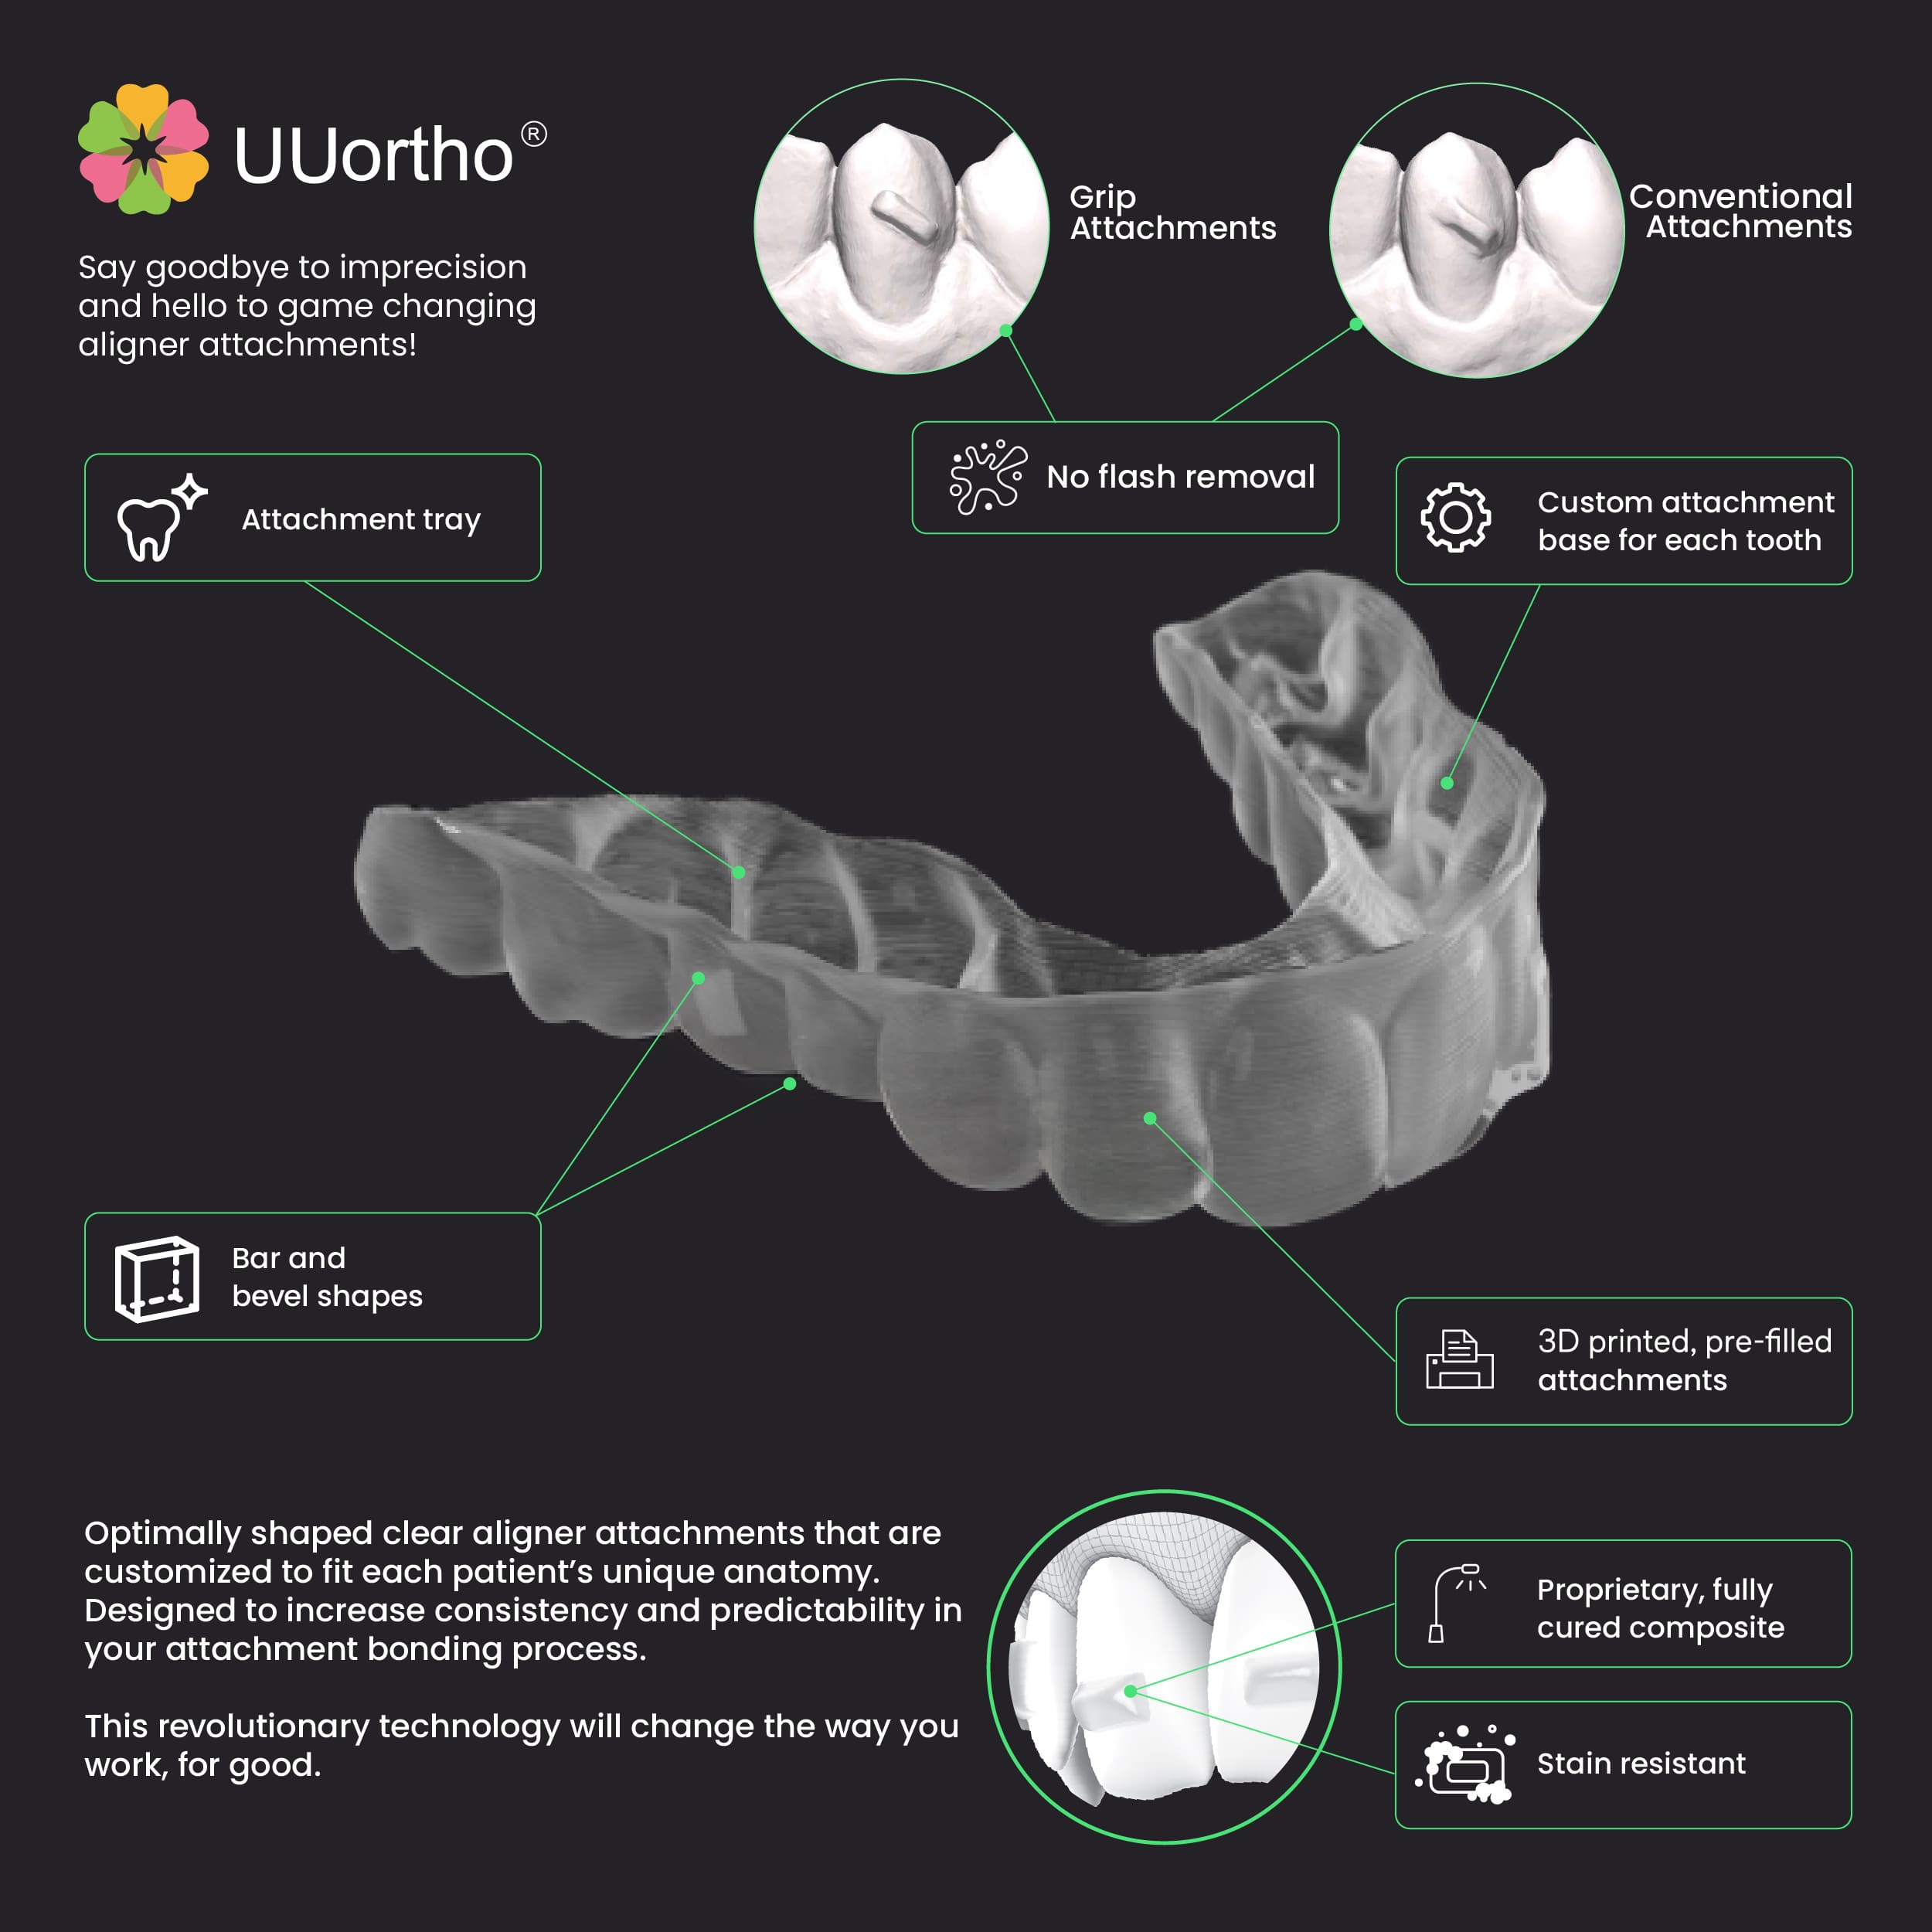

Thin, BPA-free TPU sheets for accurate, safe, and precise orthodontic attachment tray fabrication

A thin plastic sheet used in a thermoforming machine to make a template tray specifically for placing composite attachments on teeth during clear alig...